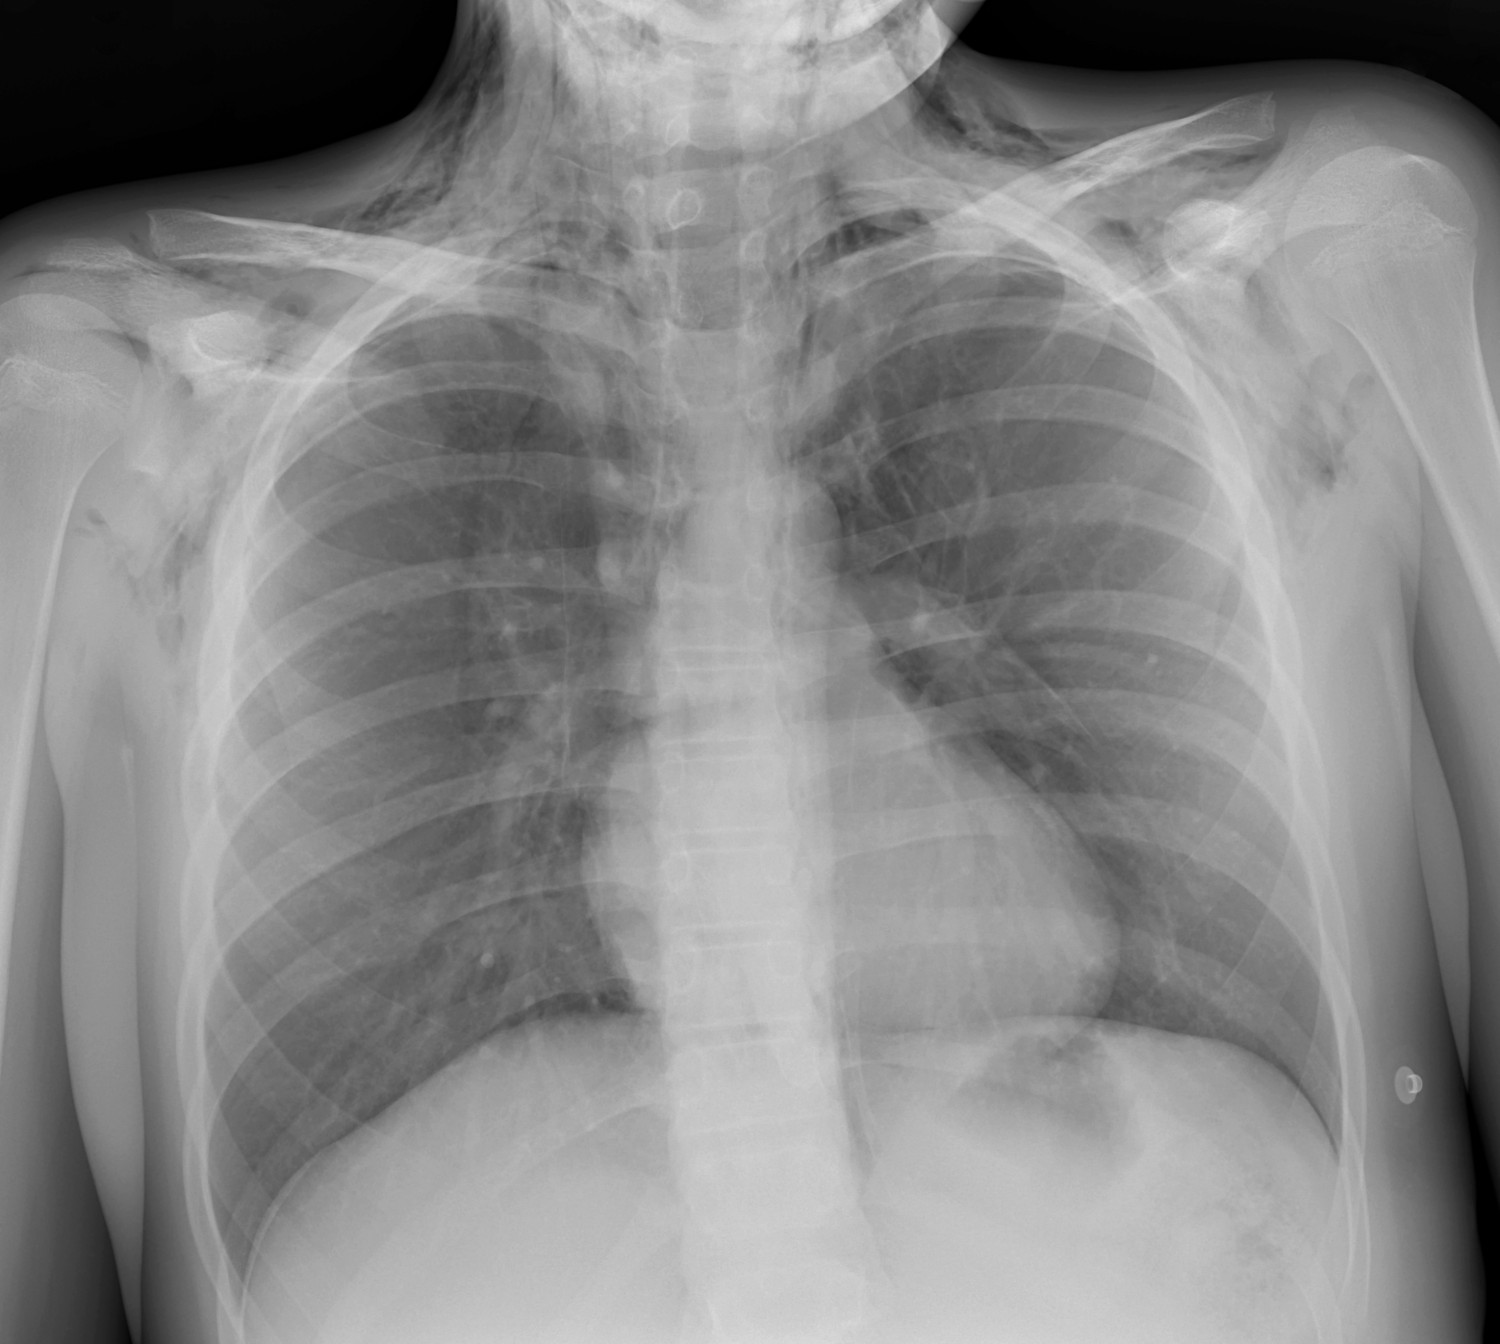

Da han ankom intensivavdelingen, svarte han på tiltale, men fremsto som forvirret og dehydrert. Han hadde rask, dyp respirasjon med frekvens 40/min (14–19/min), puls 130/min (55–95/min), stabilt blodtrykk og normal oksygensaturasjon (SpO2) (> 95 %). Det var uttalt subkutant emfysem over øvre thorax, halsen og høyre side av ansiktet. Han klarte ikke å åpne høyre øye på grunn av hevelse i øyelokk. Det var sidelike lungelyder, men hjertelydene var vanskelige å høre. Røntgen thorax (figur 1) tolket på stuen viste luft i mediastinum, bløtvevsemfysem og sannsynlig pneumothorax på venstre side.